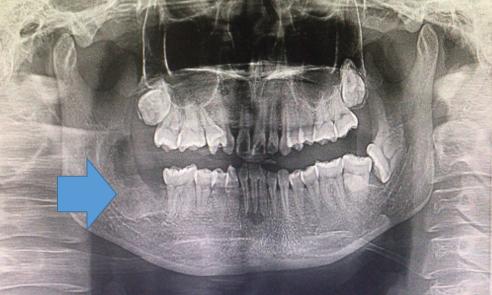

术后三个月复查,新的骨组织在形成

知识拓展:颌骨囊肿除了前述刮治外,如果囊肿范围较大,骨质膨隆明显,可采用颌骨囊肿开窗减压术。

囊肿开窗减压术:即囊性病变外表开窗,部分翻开骨质及囊壁,引流出囊液,并制造塞制器保留引流口通顺,使囊腔表里压力保持均衡,在颌骨的生理活动状态下,囊肿外周骨新建,颌骨外形改建,囊腔减小,形态得以恢复。 开窗6-18个月后,视情况是否行II期手术。